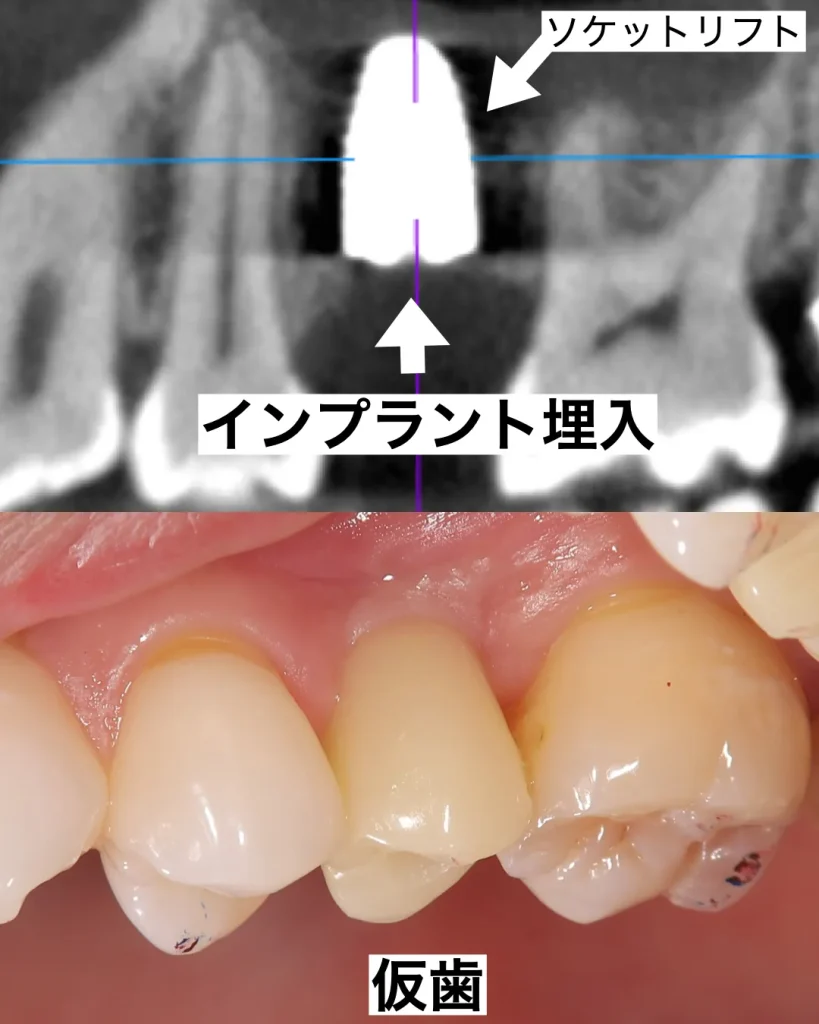

インプラント手術は抜いてその日にインプラントを埋入する抜歯即時インプラントを行いました。この手術のメリットは、抜歯する手術とインプラントを入れる手術を同時に行うことができ、痛みが少なく出血も少なくて済む点です。当院ではこの方法を第一選択として採用し、患者様の治癒期間と痛みを最小限にするようにしています。さらに、今回はソケットリフトと呼ばれるインプラントの先の上顎洞粘膜を押し上げる手術も同時に行いました。

1ヶ月後にISQ値とPT値と呼ばれる、インプラントと骨との結合度合いを測定する機械で確認した後、問題なくしっかりとした値が出たので、仮歯を装着しました。

患者様は最終的な被せ物は白めが良いとのことで、仮歯よりもかなり白いセラミックのインプラントを選択されました。治療期間も3ヶ月かからず、痛みもほとんどなかったので大変喜ばれていました。今は半年に1度のメインテナンスに通院され、定期的にクリーニング・歯周病チェック・噛み合わせ調整を行い、長期的に健康な状態を維持されています。